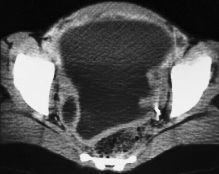

Radiología Caso 4

Caso 4

Case 4

Óscar Rueda, Eduardo Fraile, Fernando Gutiérrez